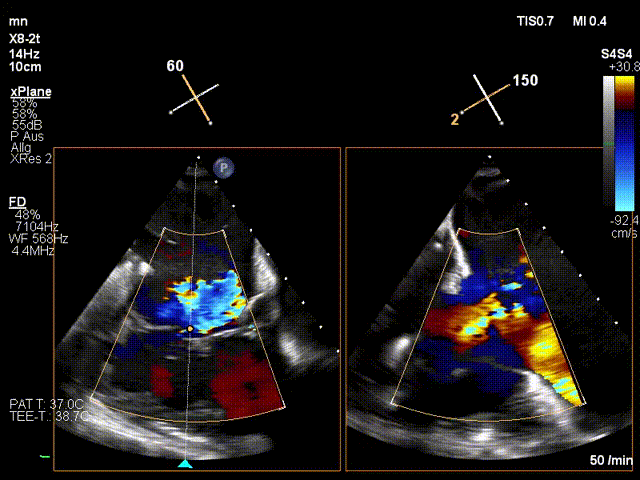

手術(shù)在全麻狀態(tài)下進行。在加拿大圣保羅醫(yī)院的Anson Cheung教授的指導(dǎo)參與下,術(shù)者采用經(jīng)右側(cè)頸靜脈入路的方式將輸送器送入患者心臟內(nèi),在TEE及DSA引導(dǎo)下調(diào)整輸送器頭端角度,使得輸送器與三尖瓣瓣環(huán)平面垂直。在輸送器進入右心室后釋放室間隔錨定裝置,而后釋放瓣葉夾持件(2個耳片結(jié)構(gòu))成垂直狀態(tài)。在TEE及DSA確定夾持件固定至三尖瓣葉根部且位于右室側(cè)后釋放人工瓣心房側(cè)盤片。隨后調(diào)整瓣膜同軸性以及室間隔錨定件位置(貼合室間隔),前推藏針管并固定,進而釋放室間隔錨定裝置,并再次確認瓣膜位置、穩(wěn)定性及同軸性,合攏輸送鞘后撤出輸送器,完成LuX-Valve Plus人工三尖瓣瓣膜的植入。

LuX-Valve Plus經(jīng)血管三尖瓣置換系統(tǒng)本次“出海”圓滿完成,術(shù)后Jörg Hausleiter教授對LuX-Valve Plus經(jīng)血管三尖瓣置換系統(tǒng)的器械性能和治療效果大為稱贊,認為LuX-Valve Plus的手術(shù)體驗非常好。術(shù)后即刻超聲顯示三尖瓣反流消失,血流動力學(xué)改善顯著,患者恢復(fù)快。Anson Cheung教授也肯定了LuX-Valve Plus術(shù)中操作的便捷性,認為LuX-Valve Plus容錯率高,對術(shù)中影像的依賴較小,后期希望可以更多的應(yīng)用LuX-Valve Plus三尖瓣置換系統(tǒng)于臨床實踐,讓更多的三尖瓣重度反流患者盡早獲益,改善預(yù)后。